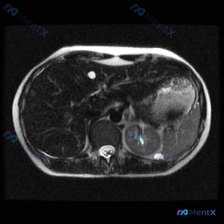

整理了一份有点意思的读片分析,核心是“关注点错位”——临床问的是脾脏病变,但影像的真正异常在肝脏。 一、先看影像基础信息 - 序列:腹部MRI轴位T1加权像 - 覆盖范围:上腹部(肝左/右叶部分、脾脏、胰腺体尾、胃泡、腹主动脉) - 图像质量:信噪比良好,无明显运动伪影 二、关键影像表现(按事实优先...

整理了一份腹部MRI-T1加权轴位平扫的病例资料,同时结合了完整的分析思路,分享出来一起讨论。 核心影像表现 1. 脾脏:体积增大,内部可见多发明显的低信号结节影/斑片影,呈弥漫性分布,边界相对模糊 2. 肝脏:肝实质信号欠均匀,可见多发斑点状、类圆形低信号影散在分布 3. 右侧肾上腺区:可见类圆形...